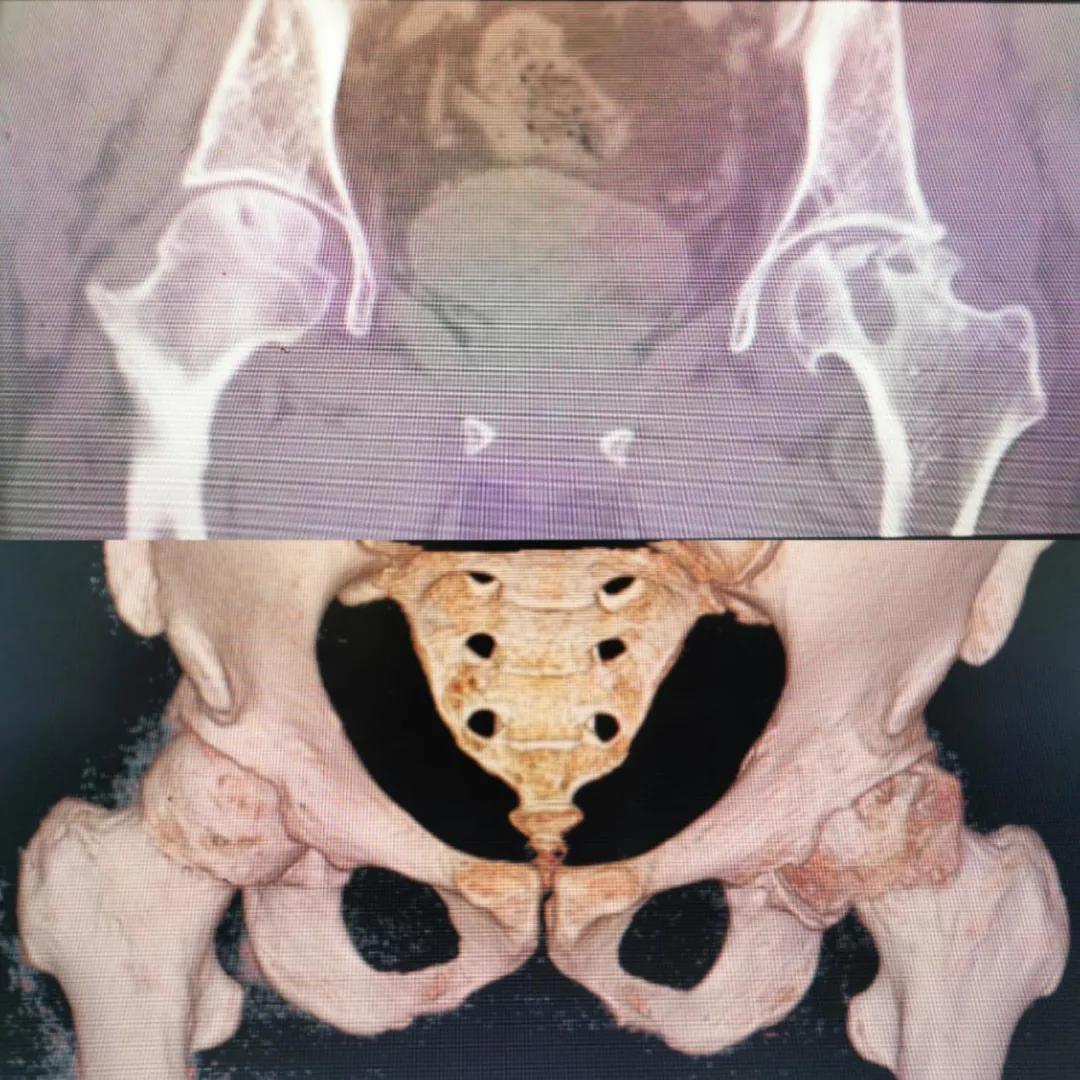

圖片(圖為患者入院時髖部CT檢查)

入院急查血結果提示炎癥反應,感染較重,凝血功能及肝功均不同程度損害;髖關節(jié)磁共振(MRI)檢查提示雙側股骨頭缺血壞死,繼發(fā)髖關節(jié)炎,左側髖周軟組織腫脹。醫(yī)療團隊給出的初步診斷為膿毒血癥、股骨頭缺血性壞死、軟組織感染、皮膚潰瘍及閉孔神經損傷。

追溯病史,患者訴前不久曾用蜂蜇療法治療股骨頭壞死,每日4次,每次100只蜜蜂蜇雙臀部、髖部,這才導致了病情急劇進展。查明了來龍去脈,我院智能微創(chuàng)骨科醫(yī)護團隊與患者家屬積極溝通病情,給予特殊級抗生素抗感染以及消腫、止痛等支持治療,同時對潰瘍創(chuàng)面進行專業(yè)、規(guī)范的清創(chuàng)、換藥處理,保護創(chuàng)面降低感染程度;護理上輔助翻身,減少壓力性損傷。